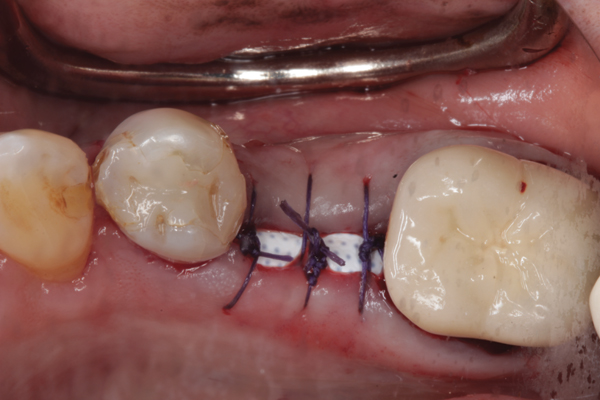

Fig 6. d-PTFE barrier in position, and the flap sutured.

Figure 6

Fig 7. At 3 weeks postoperative, notice there was no proliferation of tissue over the barrier, and the tissue was healthy.

Figure 7